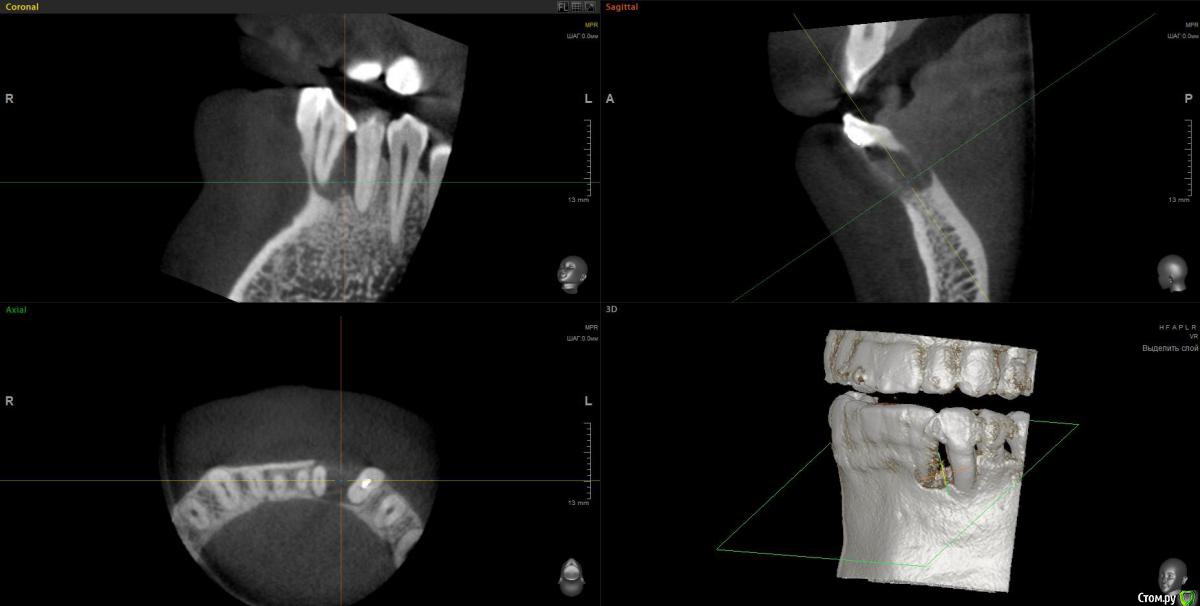

wladdX Опубликовано 3 февраля, 2017 Поделиться Опубликовано 3 февраля, 2017 Пациент 37 лет. 2,5 года назад в другом лечебном учреждении оперировали, по представленной ксерокопии карты, пародонтальную кисту. Прежних Rg-грамм нет.Сейчас следующая картина: Зубы 32 и 33 удаляем, а как далее правильно поступить?Каким способом лучше возместить дефект кости? Ваше мнение, коллеги? Ссылка на комментарий

wladdX Опубликовано 6 февраля, 2017 Автор Поделиться Опубликовано 6 февраля, 2017 Боюсь, что ничего из предложенного выше не выйдет. Вестибулярная и язычная стенки альвеол отсутствуют почти полностью. Зубы подвижны, почти постоянное гноетечение из карманов. Ссылка на комментарий